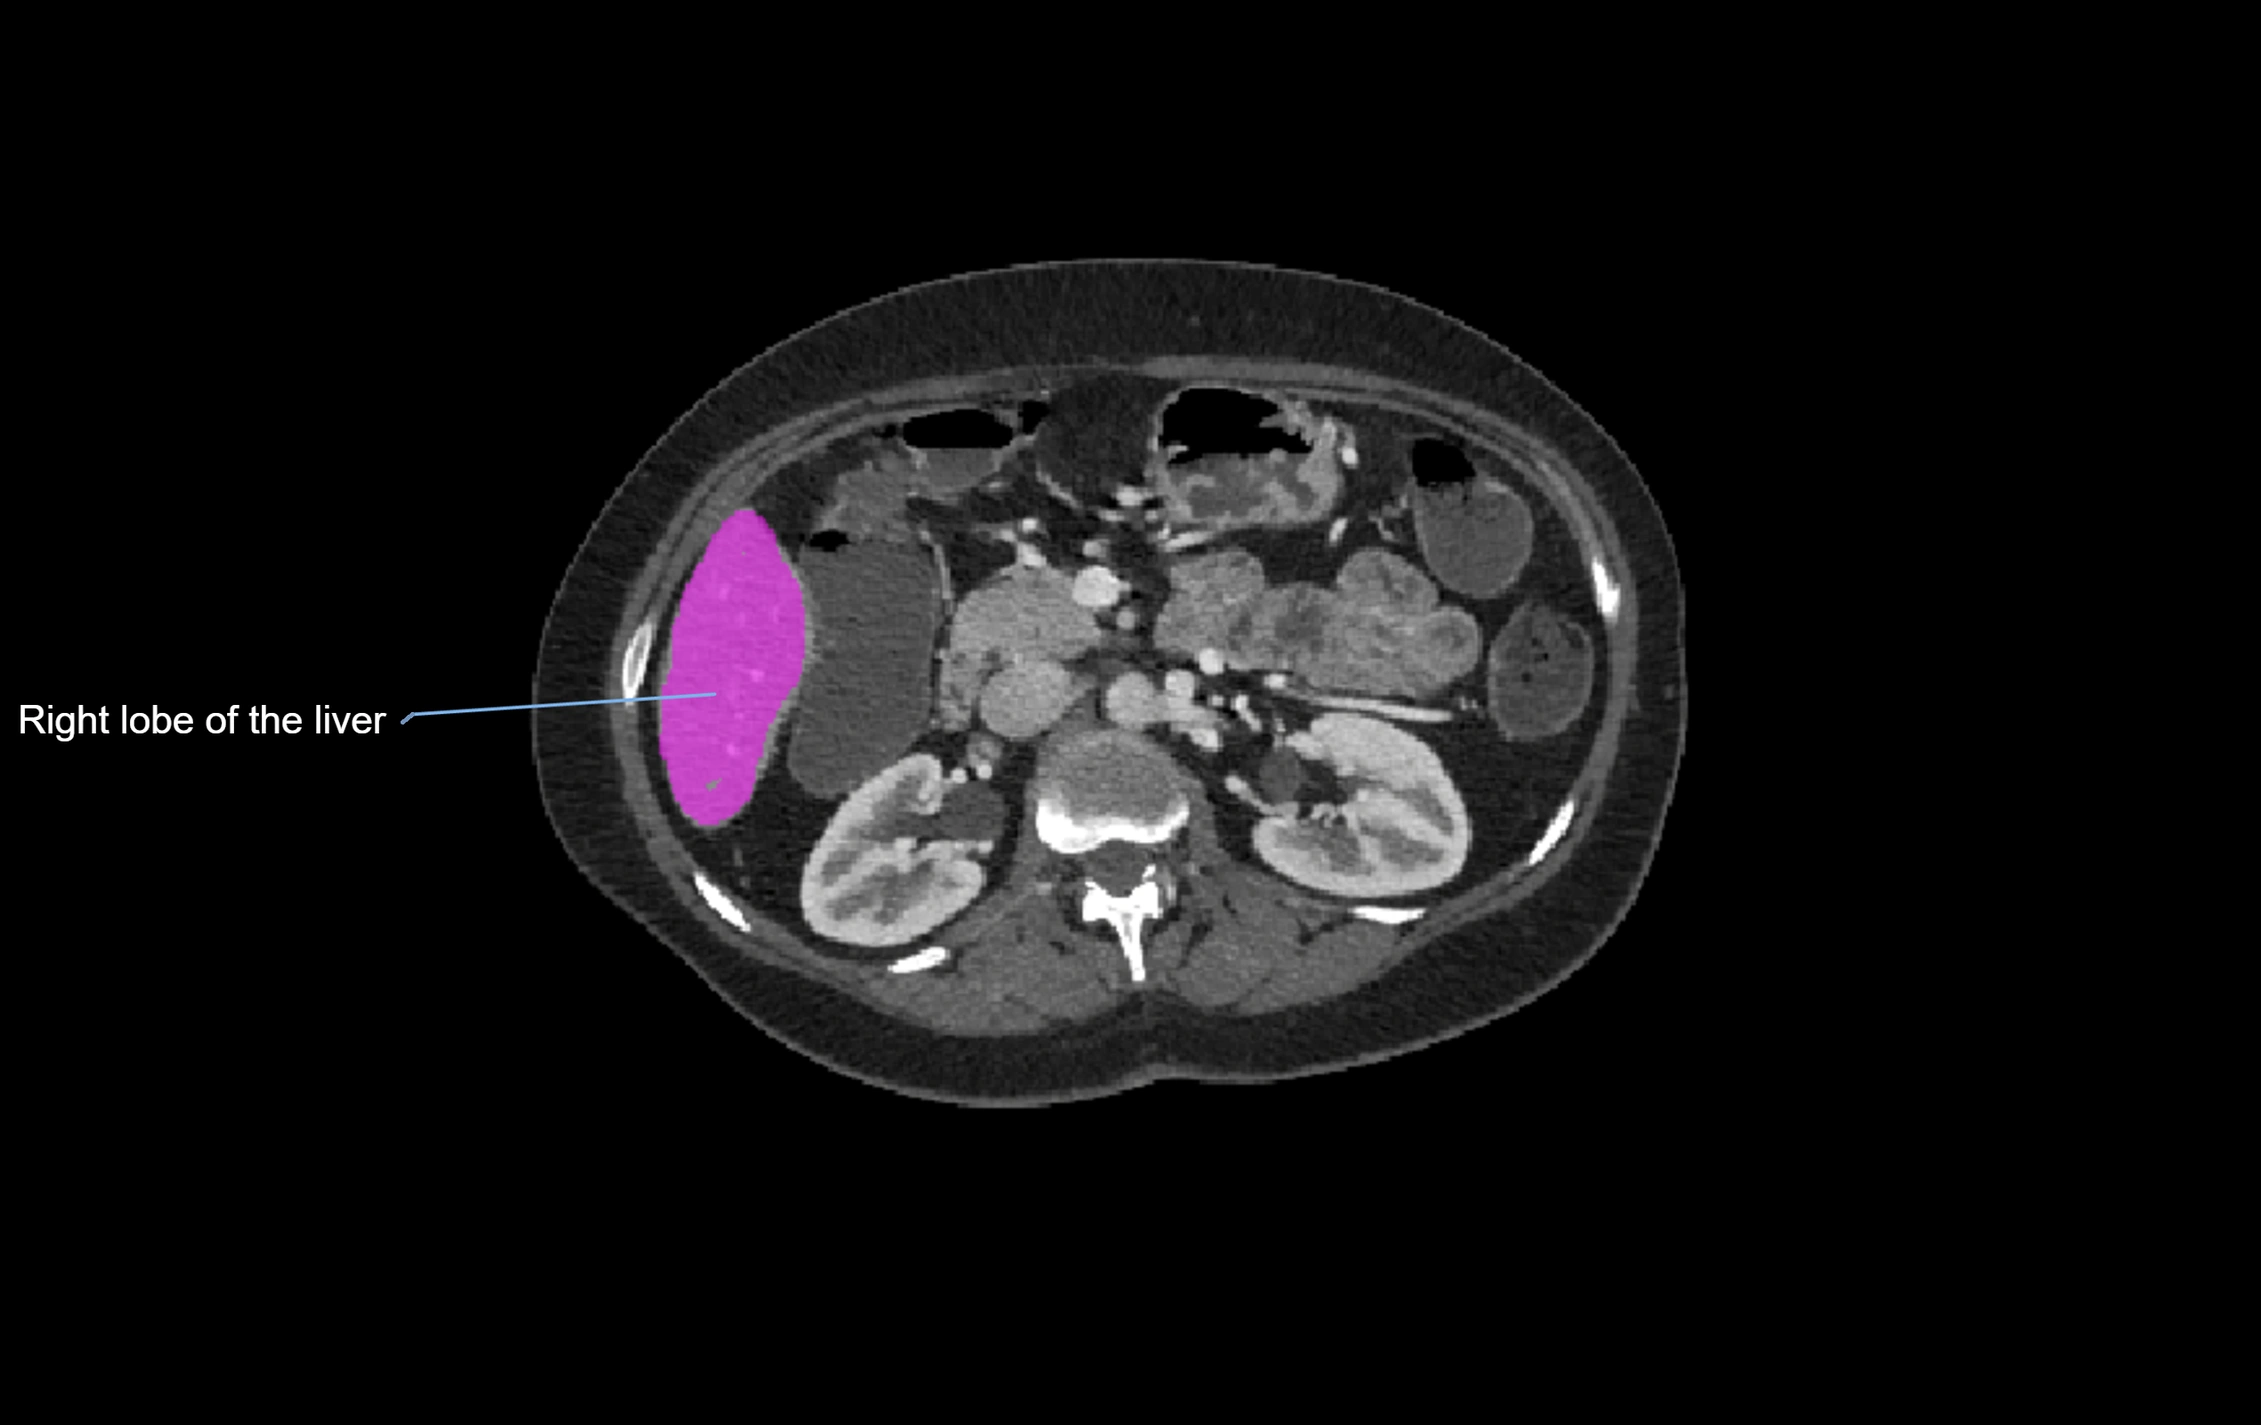

CT Image

image